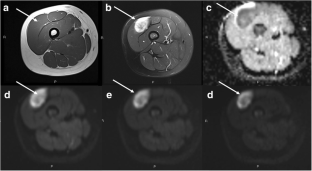

Fig. 1